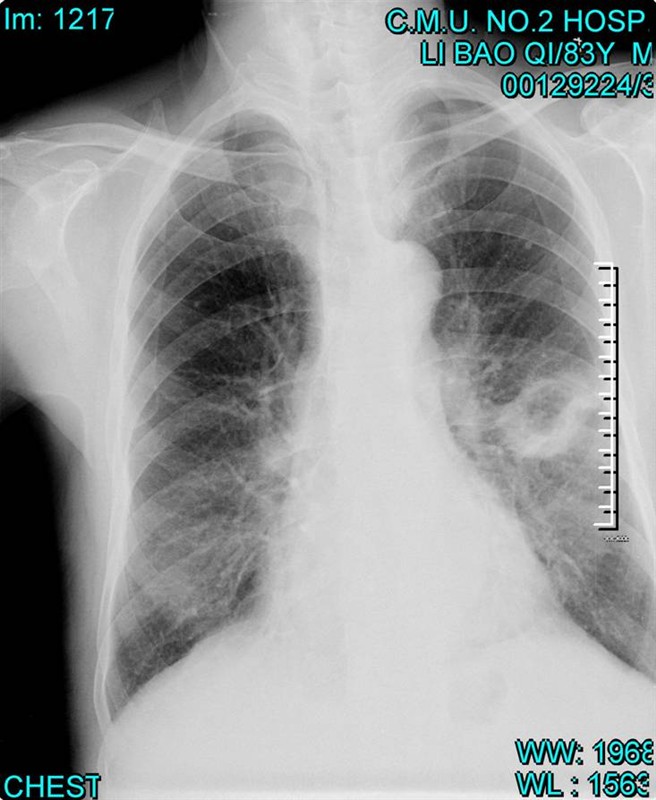

照片名称:左上叶下舌段肺癌——空洞